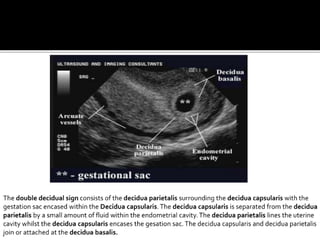

DOUBLE DECIDUAL SIGN

Described by Nyberg et al, as a method to differentiate between an

early IUP and the pseudosac of the ectopic pregnancy.

 Visualized by about 5.5 – 6 weeks of GA

 It is based on visualization of two echogenic rings.

 The inner ring is formed by the gestational sac as an

echogenic ring formed by the decidua capsularis and

chorionic laeve eccetrically.

 The outer ring is formed by the echogenic ring of the lining

of the uterus ( formed by decidua parietalis).